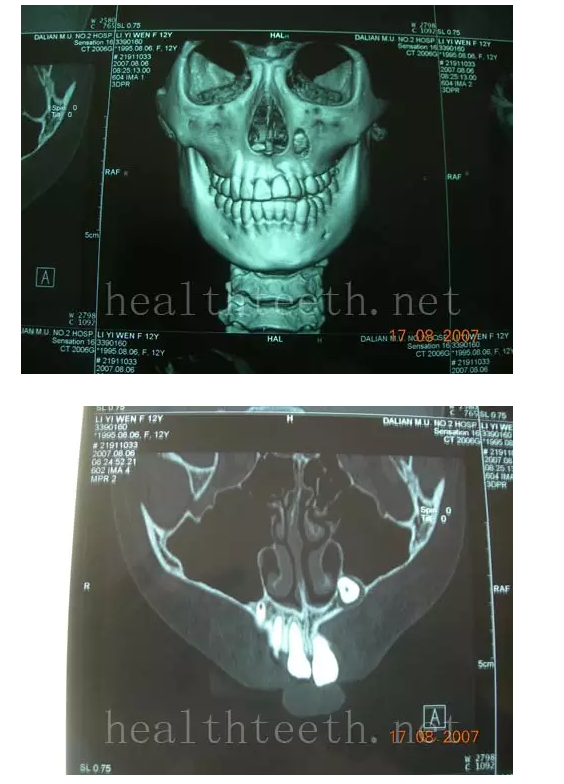

2、埋伏牙

左上乳3滯留,恒3未見萌出,曲面斷層片顯示牙齒埋伏

通過CT片確定埋伏牙齒具體的位置,顯示距離左側(cè)上頜竇很近,偏唇側(cè),這為手術(shù)定位提供了方便

手術(shù)中切斷、完整拔出,未損傷上頜竇